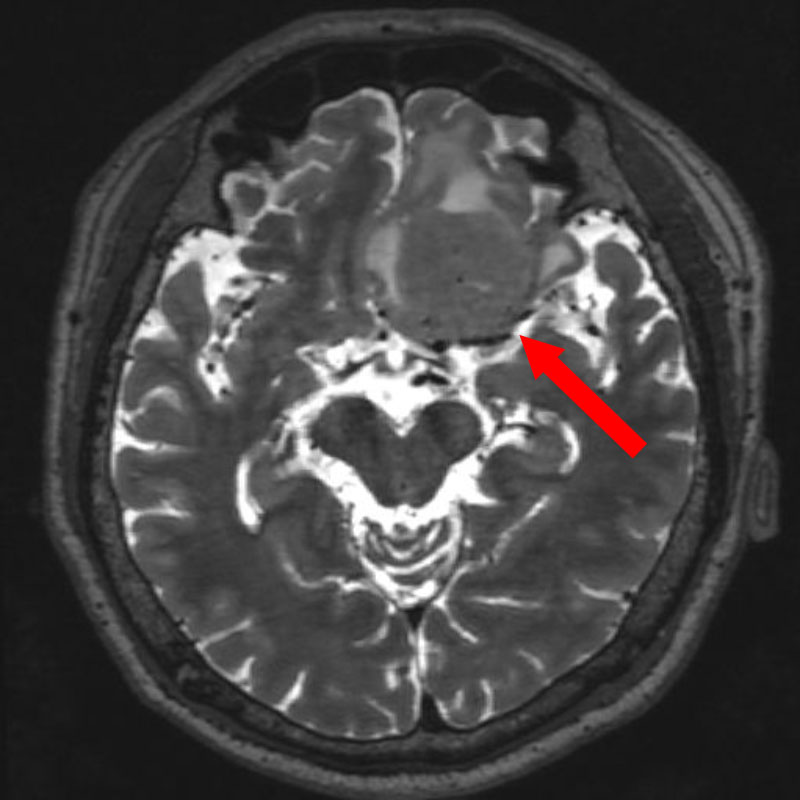

707

'25年12月

80代

髄膜腫

頭蓋内腫瘍摘出術

No.’25_109 手術前1

No.’25_109 手術前2